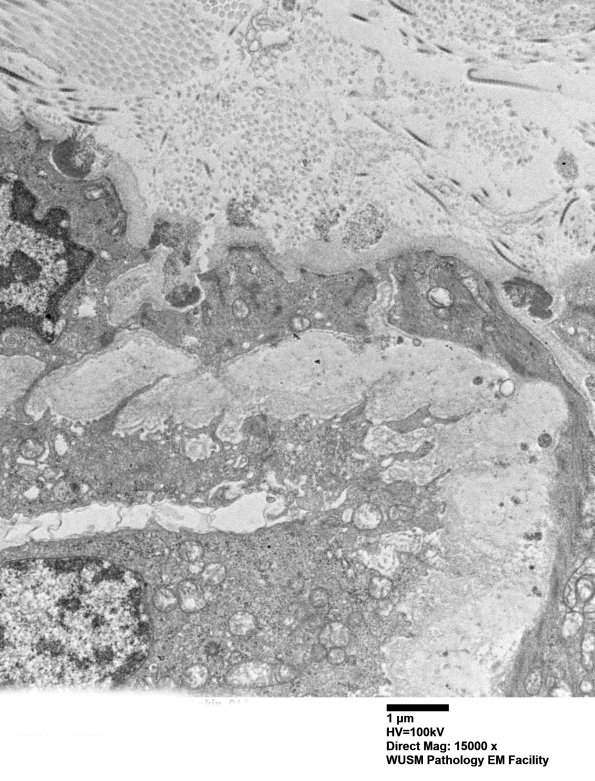

11E5B Higher magnification of the vascular wall showing several GOM within the basal membrane of smooth muscle cells. (electron micrograph)